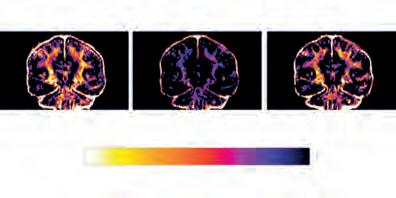

Mielinak garunaren energiagordailu gisa funtziona dezakeela frogatu dute

Ariketa fisikoa denbora luzez egiten denean, hala nola maratoi batean, nerbio-zelulek ordezko energia-iturrietara jotzen dute. Hala berretsi dute ikerketa batean. Tartean, mielinara jotzen dute, hau da, nerbio-zuntzak inguratzen dituen egiturara. Ikerketan, hainbat zentrotako ikertzaileak aritu dira elkarlanean (EHU, CIC biomaGUNE, CIBERNED, Biobizkaia, Achucarro…).

Zenbait maratoi-lasterkariren garunak eskaneatu zituzten, lasterketaren aurreko eta ondorengo egunetan eta handik bi astera. Hala, ikusi zuten maratoia egiteak mielina-edukia murrizten duela. Handik bi astera, ordea, mielina-mailak ia lehengoak ziren. Dena dela, ikertzaileek ohartarazi dute esfortzua gehiegi luzatzeak ondorio funtzionalak izan ditzakeela garunean.

Nolanahi ere, ondorioztatu dute mielina ordezko energia-biltegi bat izan daitekeela. Eta adierazi dute horrek garunaren eskakizun energetikoei buruzko ikuspegi berri bat ireki duela. Aurreratu dute ireki ditzakeela ildo berri batzuk neuroendekapenezko gaixotasunak aztertzeko eta tratatzeko ere, hala nola esklerosi anizkoitza eta beste gaixotasun desmielinizatzaile batzuk.

Lasterkari baten RMN bidezko irudiak. Erdikoan, esfortzuak eragindako mielina-galera nabari da. ARG.: Pedro Ramos Cabrer/CICbiomaGUNE.

Ariketa aurretik Ariketa ondoren Errekuperazioa Mielina

Gehiago Gutxiago